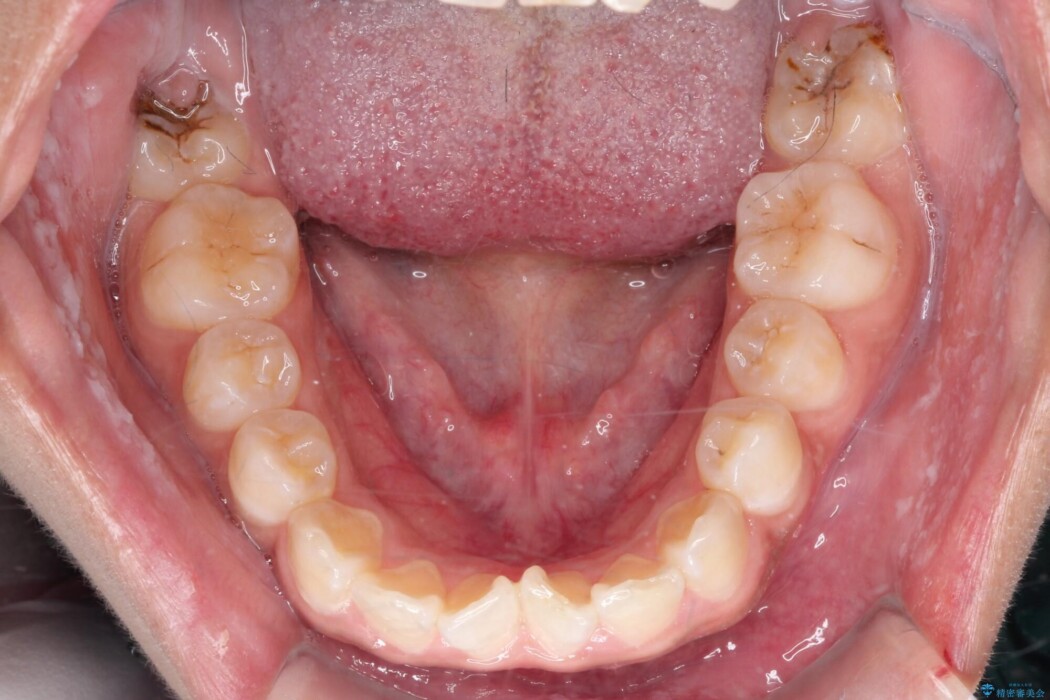

矯正検査の結果、歯列全体のスペースが不足しており、これが突出感の原因となっていました。

無理に歯を並べても口元の突出感は解消されないため、上下左右4番を抜歯しスペースを確保、目立ちにくい審美ワイヤー装置にて治療を行うこととしました。

抜歯によって得たスペースを活用し、審美ワイヤーによる繊細な角度調整を行いながら前歯を後方へ移動。

突出していた口元のボリュームを段階的に抑制し、理想的なバランスへと導きました。